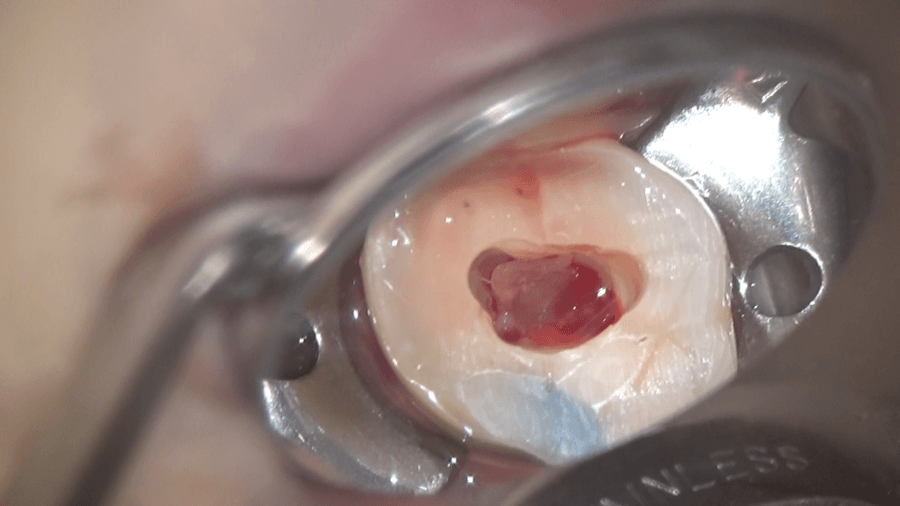

内部にあるゼリー状の組織、歯髄が見えます。これがいわゆる神経です。

もう少し大きくすると、内部に石のようなものが確認できます。

触ると動きます。